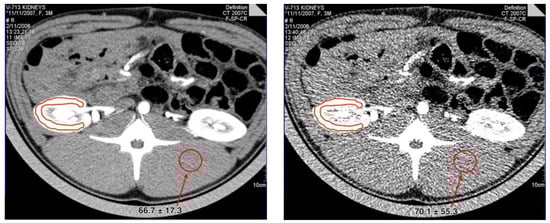

In Section 2.1, for CT imaging technology, we introduce its advantages. CT is one of the most popular tumor imaging techniques to date, but it has caused concerns due to its extensive radiation. Studies have shown that the projected radiation to body organs during CT scans is very high in the thyroid, lung, mammary gland, and esophagus, and high-dose CT promotes the proliferation of mammary gland tissue and cells to a higher extent. Children and young women are more susceptible to radiation damage, and the risk of malignant tumors after radiation is increased [56,57,58,59]. This has made people reluctant to use CT scans for fear of cancer or genetic disease. Therefore, many clinical examinations use low-dose CT (LDCT) imaging to minimize radiation-related risks without substantially damaging the screener’s body [60,61]. Low-dose CT scanning is an imaging method that considerably reduces the X-ray dose on the basis of a conventional dose of CT scanning, and it mainly reduces the dose by reducing the current and voltage intensity and irradiation time of the X-ray emitter tube, which leads to serious artifacts and noise pollution in the projected data. As a result, the contrast of low-dose CT images is lower, and the clarity is poor. Compared with conventional-dose CT images, the nodules are not obvious, and the tissue surrounding the nodules is poor. Figure 4 and Figure 5 show the CT at the conventional-dose level and the CT at the 1/10-dose level, respectively. Through comparison, it was found that the currently commonly used CT image datasets have disadvantages, such as high noise, burr phenomenon at the image edge, excessive particle noise, and poor contrast.

Figure 4.

The top image is taken from FLAIR’s strong magnetic field, and the bottom image is taken from FLAIR’s weak magnetic field in the same position from left to right.

Figure 5.

The picture on the left is a CT at the regular-dose level, and the picture on the right is a CT at the 1/10-dose level.